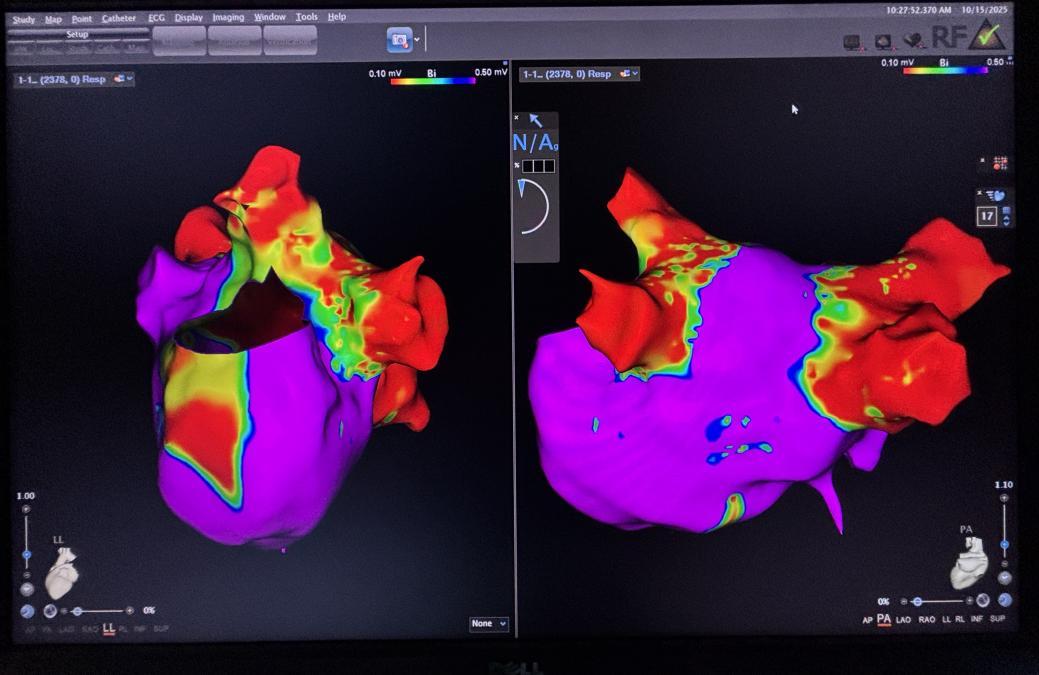

心腔超声左房建模